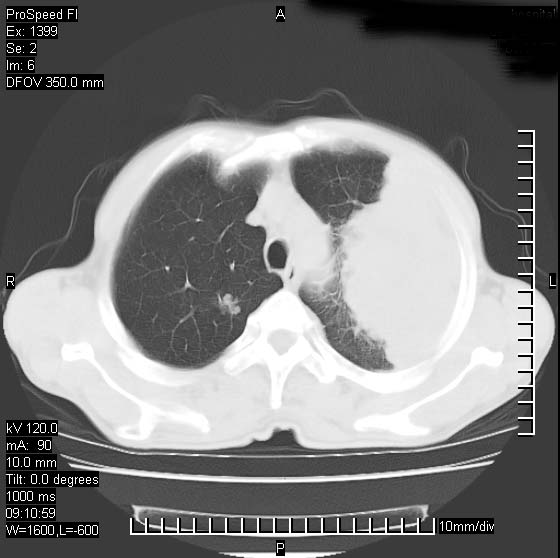

以下是引用卜一在2007-1-19 9:55:00的发言:[br]左肺沿胸膜下巨大肿块影,边缘呈分叶征,纵隔内见肿大淋巴结,右肺内另见一不规则结节影 .考虑:左肺周围性肺癌伴纵隔 右肺内转移.

以下是引用rgsyyf在2007-1-19 11:05:00的发言:[br]左肺上叶见形态不规则巨大软组织肿块影,边缘呈分叶征,纵隔内隆突下见肿大淋巴结,右肺内另见一不规则结节影 .考虑:左肺周围性肺癌伴纵隔即右肺内转移.